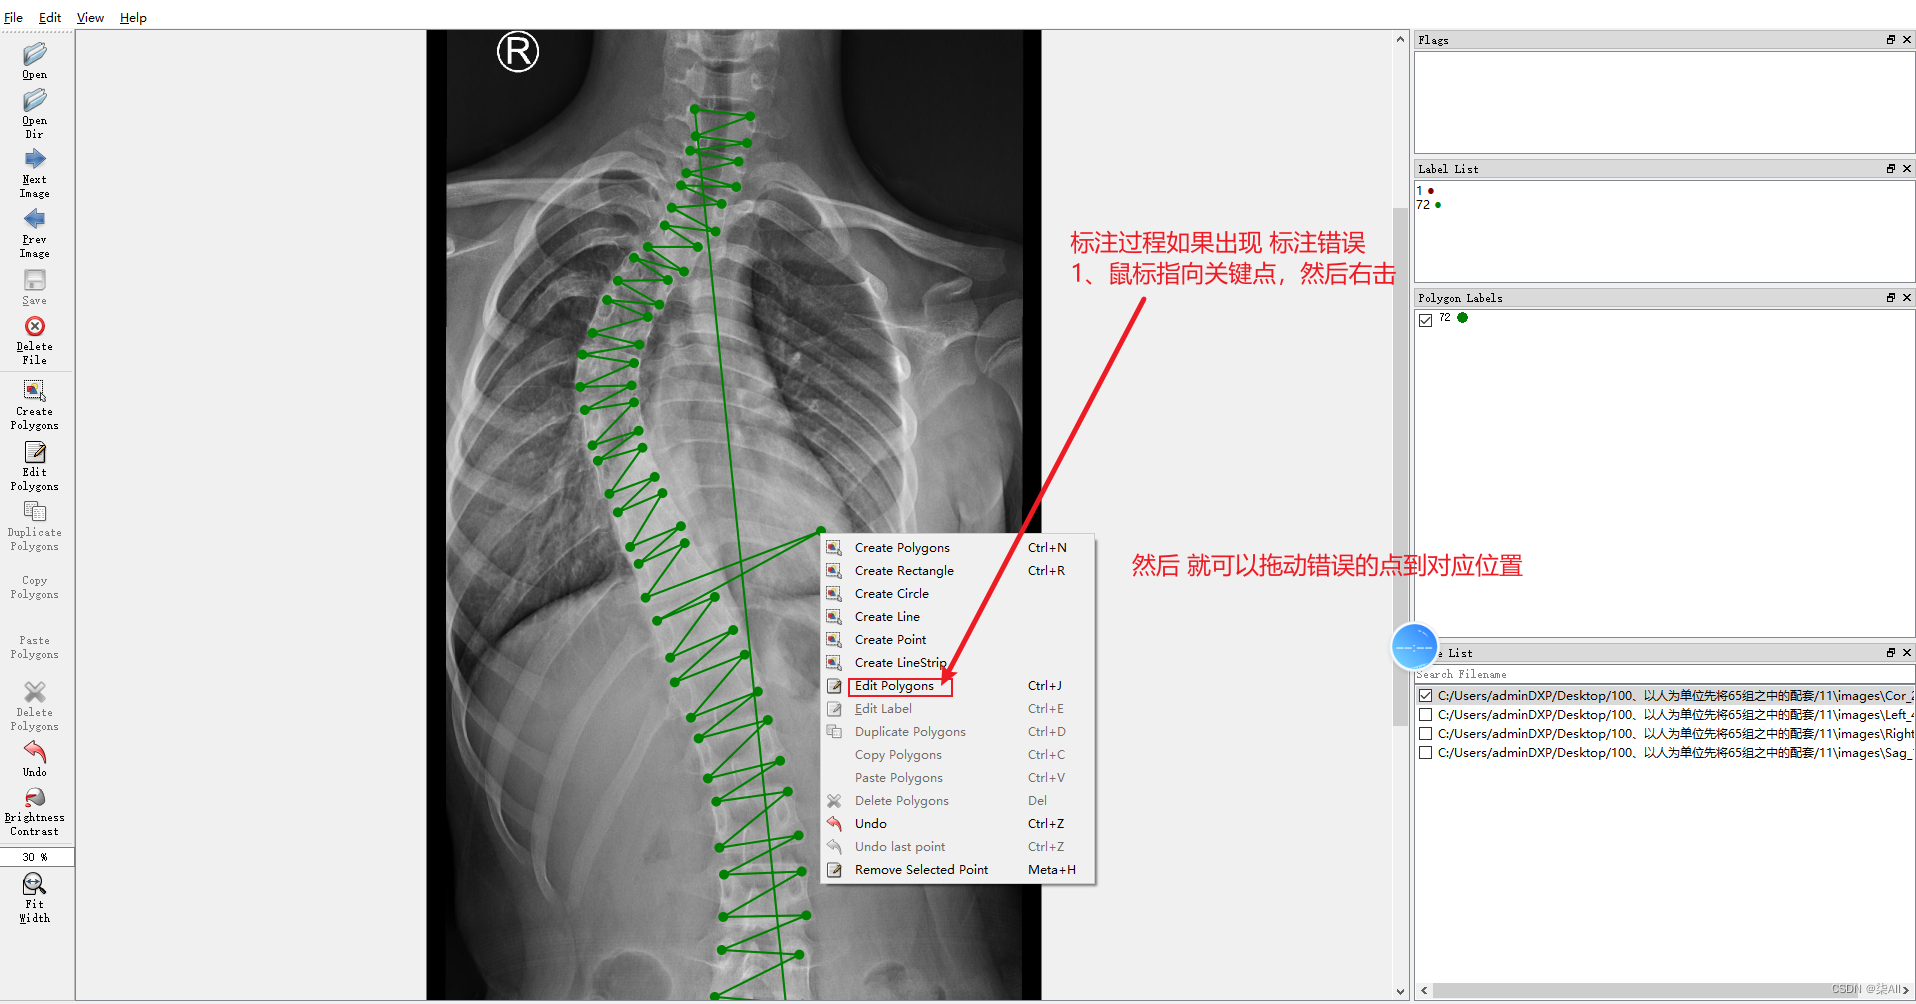

4、标注过程注意事项

4.1、关键点不小心标注的位置不对

4.2 少标记或者多标记点。进行补点或者进行删除